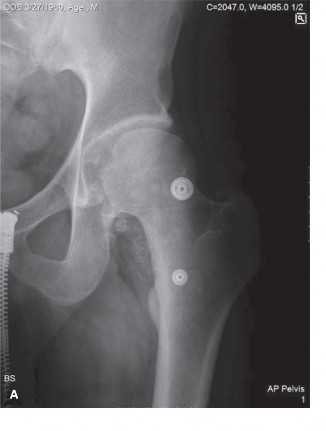

A 45-year-old male presents to your office with right hip pain. The pain worsens with activity and started in…